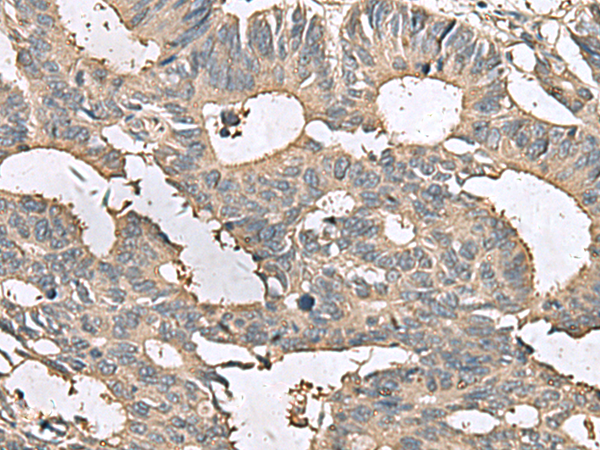

IHC positive control: |

Human cervical cancer and Human colorectal cancer |

IHC Recommend dilution: |

50-200 |